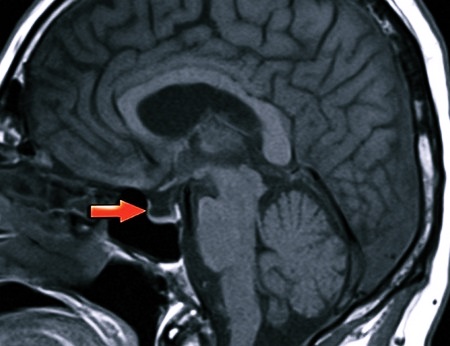

Чтобы уточнить диагноз, человека могут отправить на компьютерную томографию, рентген или магниторезонансную томографию (МРТ). Посредством такого обследования оценивается состояние гипофизарной ямки, размеры и контуры турецкого седла, наличие уплотнения дна, утолщения клиновидных отростков, определяется, имеет ли место отмирание тканей мозга, деструкция гипофиза, наличие гиперплазии и ликворного содержимого.

Все эти негативные состояния можно найти с помощью КТ или МРТ. Поэтому данные виды обследований должны быть обязательно назначены врачом при наличии соответствующей симптоматики, указывающей на вероятность развития синдрома.